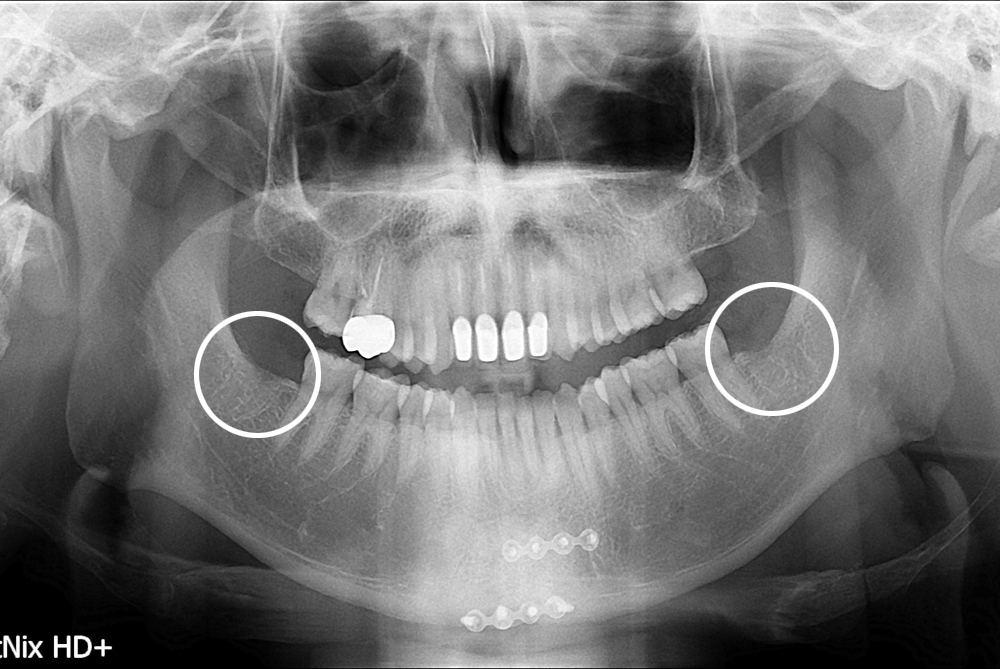

치료사례

세종치과의 진심 어린 치료는 결과로 말합니다.

실제 내원하신 환자분들의 치료 전·후 사례를 확인해보세요.

모든 치료사례 전후사진은 환자분의 동의하에 촬영되었습니다.

모든사진은 동일 환자분의 전후모습을 촬영하였으며, 사진의 밝기조절 외에 임의 수정이 없음을 알려드립니다.